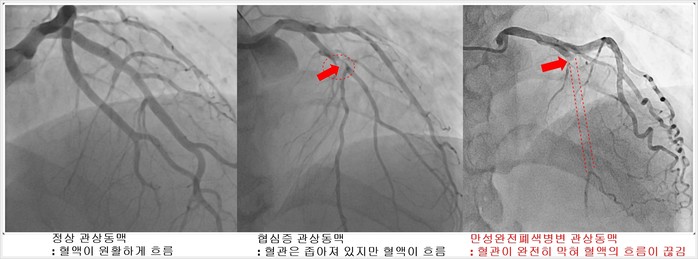

| ▲1. 정상 관상동맥 - 혈액이 원활하게 흐름 2. 협심증 관상동맥 – 혈관은 좁아져 있지만 혈액이 흐름 3. 만성완전폐색병변 관상동맥 – 혈관이 완전히 막혀 혈액의 흐름이 끊김 <이미지 서울아산병원 제공> |